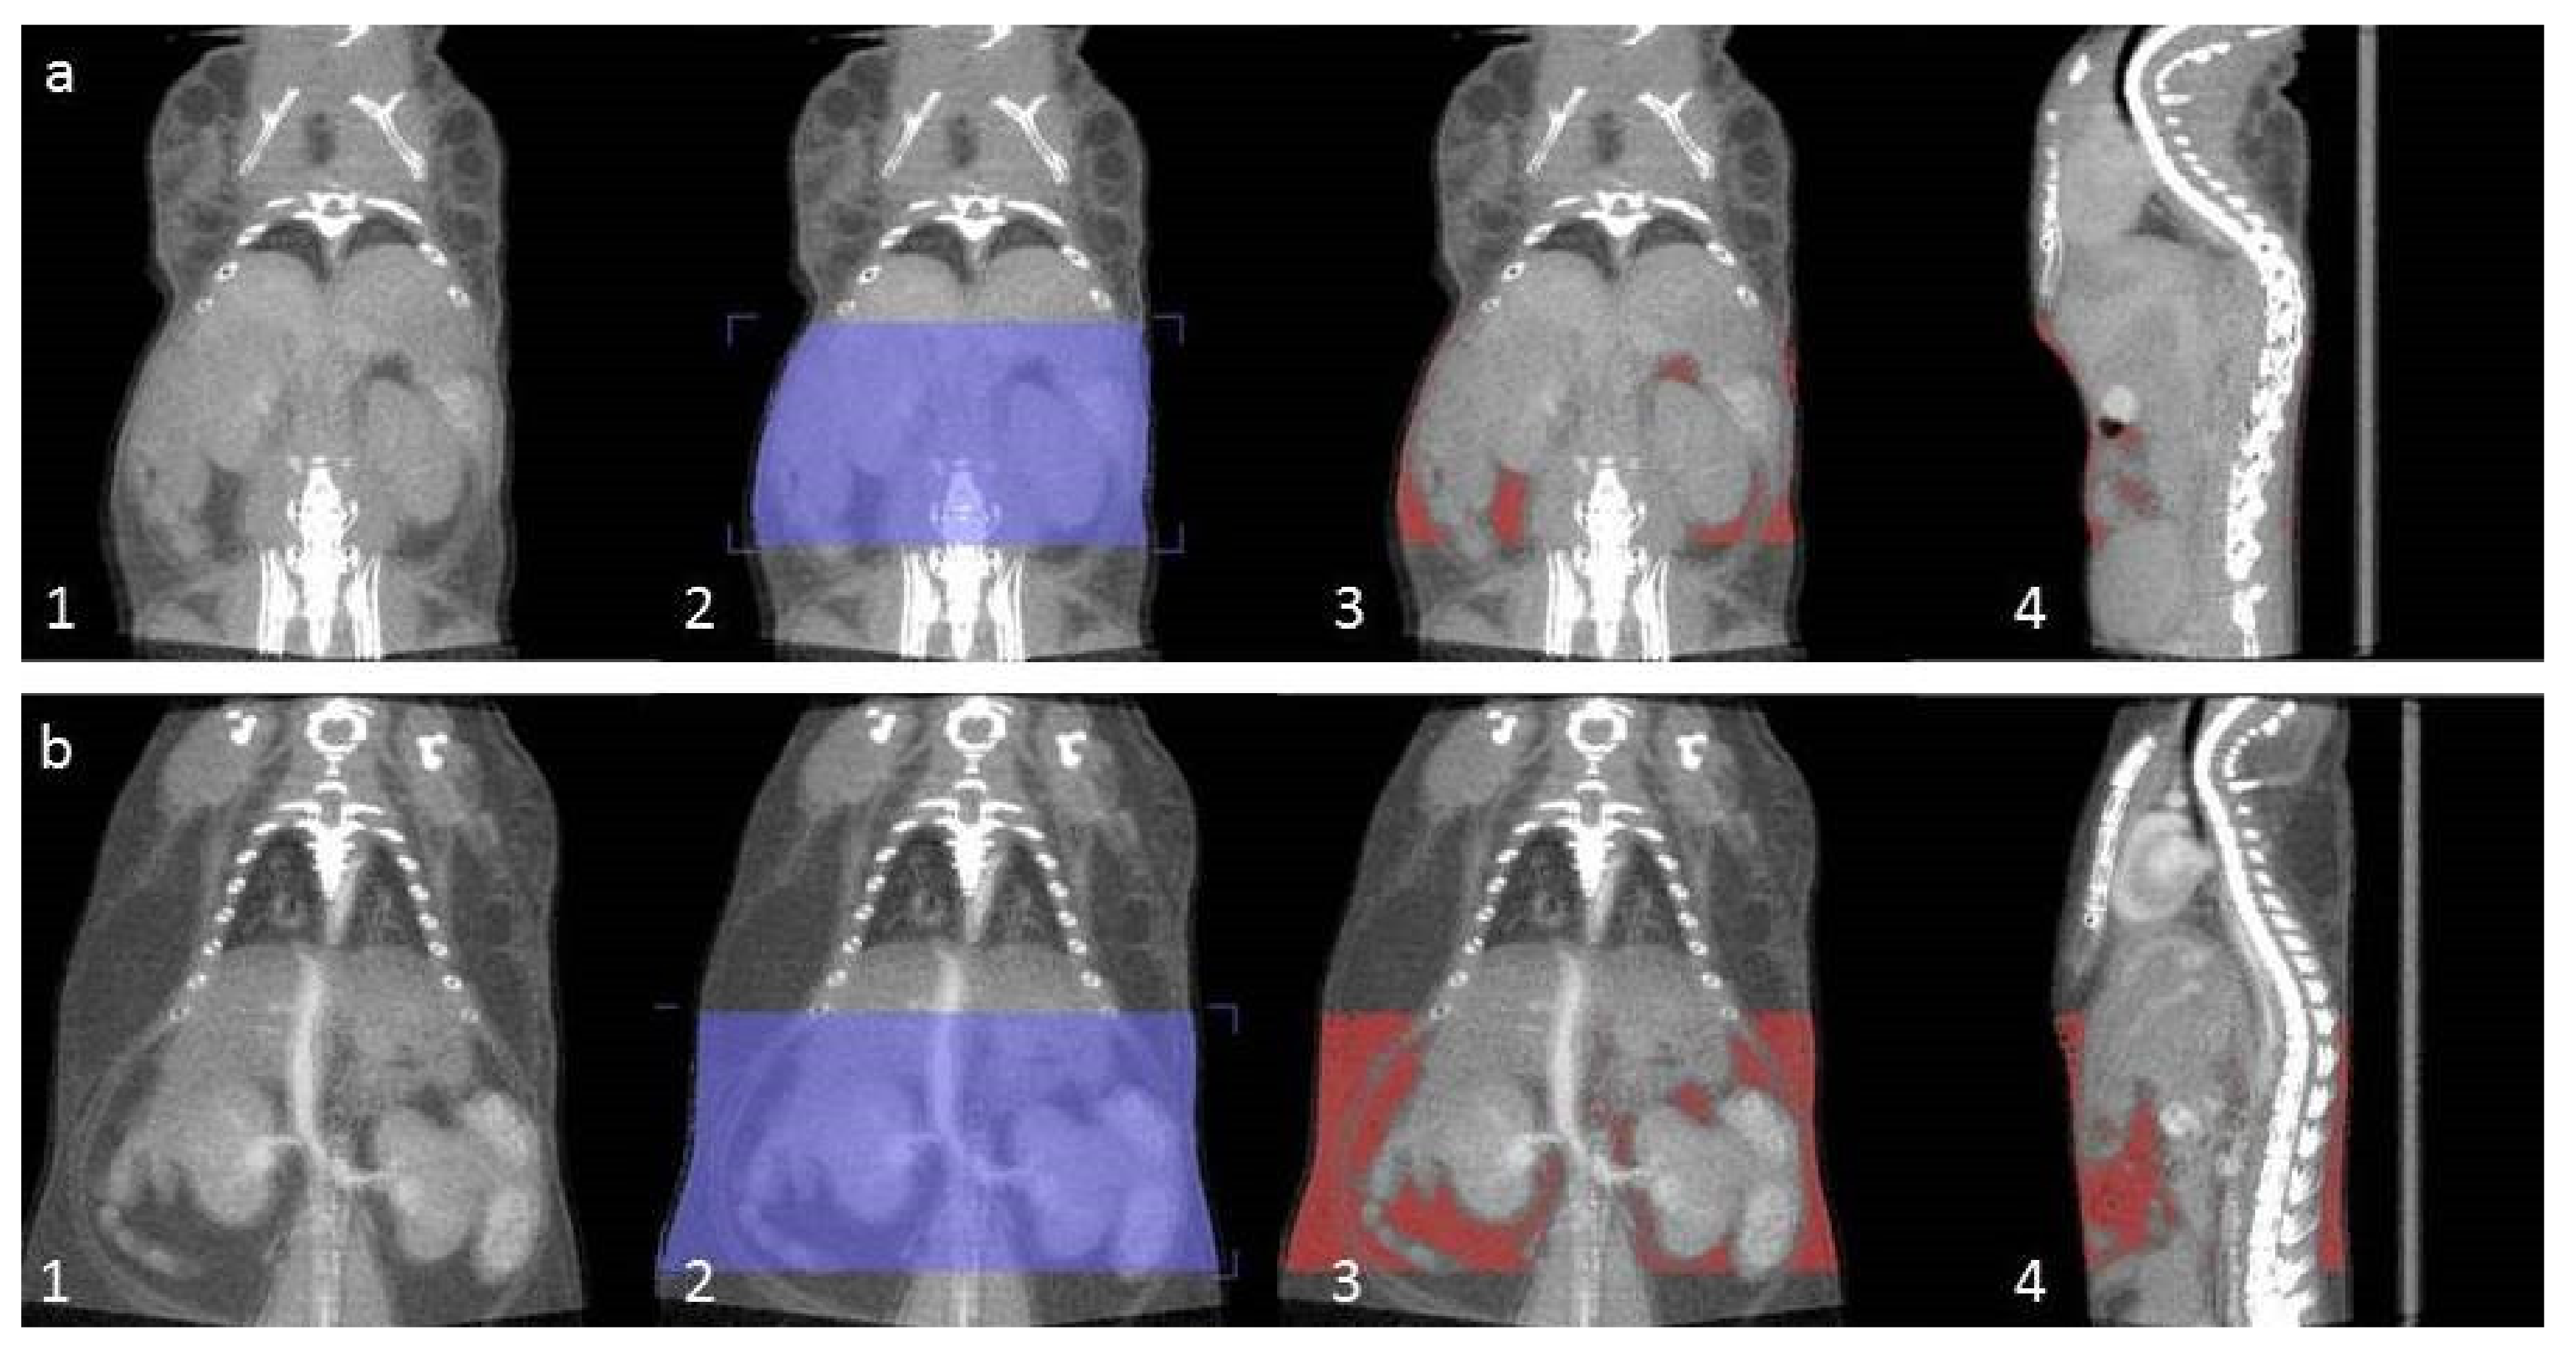

4.5. CT Analysis